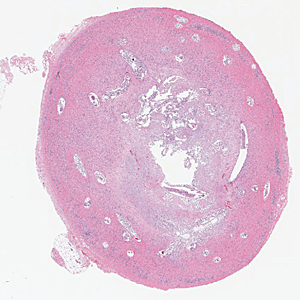

Case #384 – November 2014

A 73-year-old woman presented to a local clinic in Ghana with a skin nodule that had developed adjacent to the resection site of a previous low-grade malignant skin tumor. Biopsy specimens were collected and sent to a lab in the U.S. for histologic processing, including sectioning and staining with hematoxylin-and-eosin (H&E). Images of suspect structures were captured and sent to the DPDx Team for diagnostic assistance. Figures A–E show several of the images that were received for analysis. Neither sizes nor magnifications were provided with the images. What is your diagnosis? Based on what criteria?

Figure A